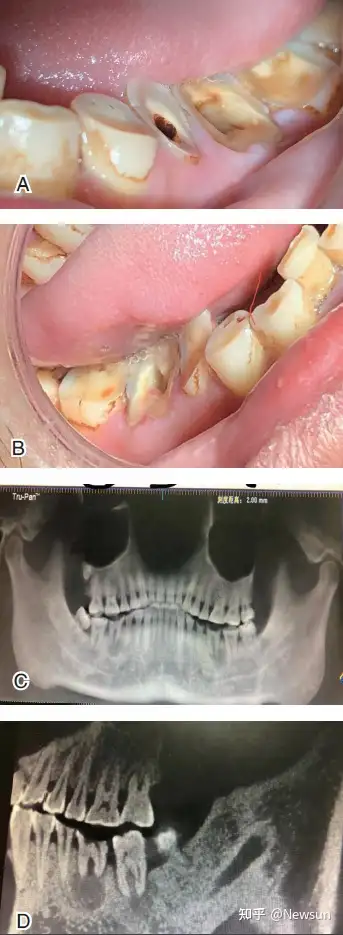

这是口腔癌?近2周发现的,我抽烟,前端时间吃了3个槟榔,不常吃

图片尺寸768x1024